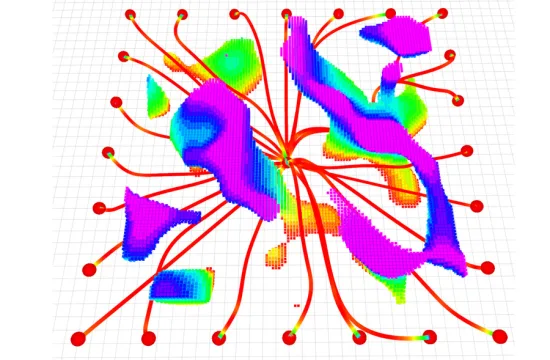

A newly NIH funded clinical trial (NCT02528942) by University of Colorado Cancer Center investigators and collaborators at Beaumont Health in Michigan and the University of Texas Medical Branch is evaluating a new method for pinpointing and sparing healthy lung tissue during lung cancer radiotherapy. The group is applying advanced image analysis techniques to 4D CT scans already performed as a standard step in targeting lung cancer radiotherapy, to map areas of lung function without additional testing.“We used to treat the lungs as a homogenous organ, as if all areas were equally important. Now we know that’s not true – there’s regionally variant function. The idea of this clinical trial is to spare functional portions of the lung during radiation by using this new imaging modality to display lung function,” says Yevgeniy Vinogradskiy, PhD, CU Cancer Center investigator and assistant professor in the Department of Radiation Oncology at the CU School of Medicine.

The answer to this challenge was 4D CT, which was developed in the early 2000s. 4D CT uses a series of images shot over time to capture the position of the lung and the tumor during all phases of the breathing cycle (time being the fourth dimension in “4D CT”). Most lung cancer patients undergo 4D CT as standard-of-care to help radiation oncologists develop a personalized plan to account for breathing motion during therapy.

While 4D CT shows tumor movement, it has not shown the function of surrounding lung tissue. Until now. The current clinical trial uses information of air movement from existing 4D CT data and “some equations,” says Vinogradskiy (diplomatically) to calculate lung function in tissue surrounding tumors.

The idea is then to take the lung function information calculated by this new imaging and use advanced radiation delivery techniques to spare the parts of the lung used for breathing. By sparing functional portions of the lung the researchers aim to significantly improve quality of life for patients that have undergone radiation treatment.